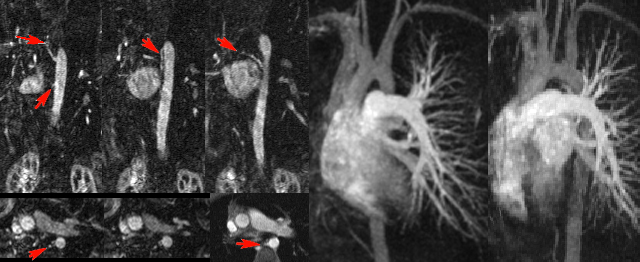

IRM cardiaque effectuée chez un patient de 48 ans en raison d’un aspect suspect de thrombus apical décelé en échographie dans les suites de plusieurs accidents emboliques systémiques : ilio-fémoral (désobstrué), mésentérique et rénal. Contexte d’EOA colique opéré et d’hépatectomie partielle pour métastases hépatiques. L’examen IRM retrouve un petit résidu thrombotique apical mobile (ciné), sans anomalie de la contraction segmentaire et révèle 2 foyers d’hypersignal pathologique post-gadolinium, enchassés dans l’épaisseur du myocarde, en inféro-latéral distal et en antéro-basal, en faveur de vraisemblables métastases cardiaques (flèches).

Récidive de rhadomyosarcome de la valve mitrale 6 mois apres resection tumorale et remplacement valvulaire mitral par une prothèse mécanique. Trois petites lésions punctiformes suspectes de métastases sont mises en évidence sur l’imagerie T1 post-gadolinium (flèches).

Récidive de rhadomyosarcome de la valve mitrale 6 mois apres resection tumorale et remplacement valvulaire mitral par une prothèse mécanique. Trois petites lésions punctiformes suspectes de métastases sont mises en évidence sur l’imagerie T1 post-gadolinium (flèches).